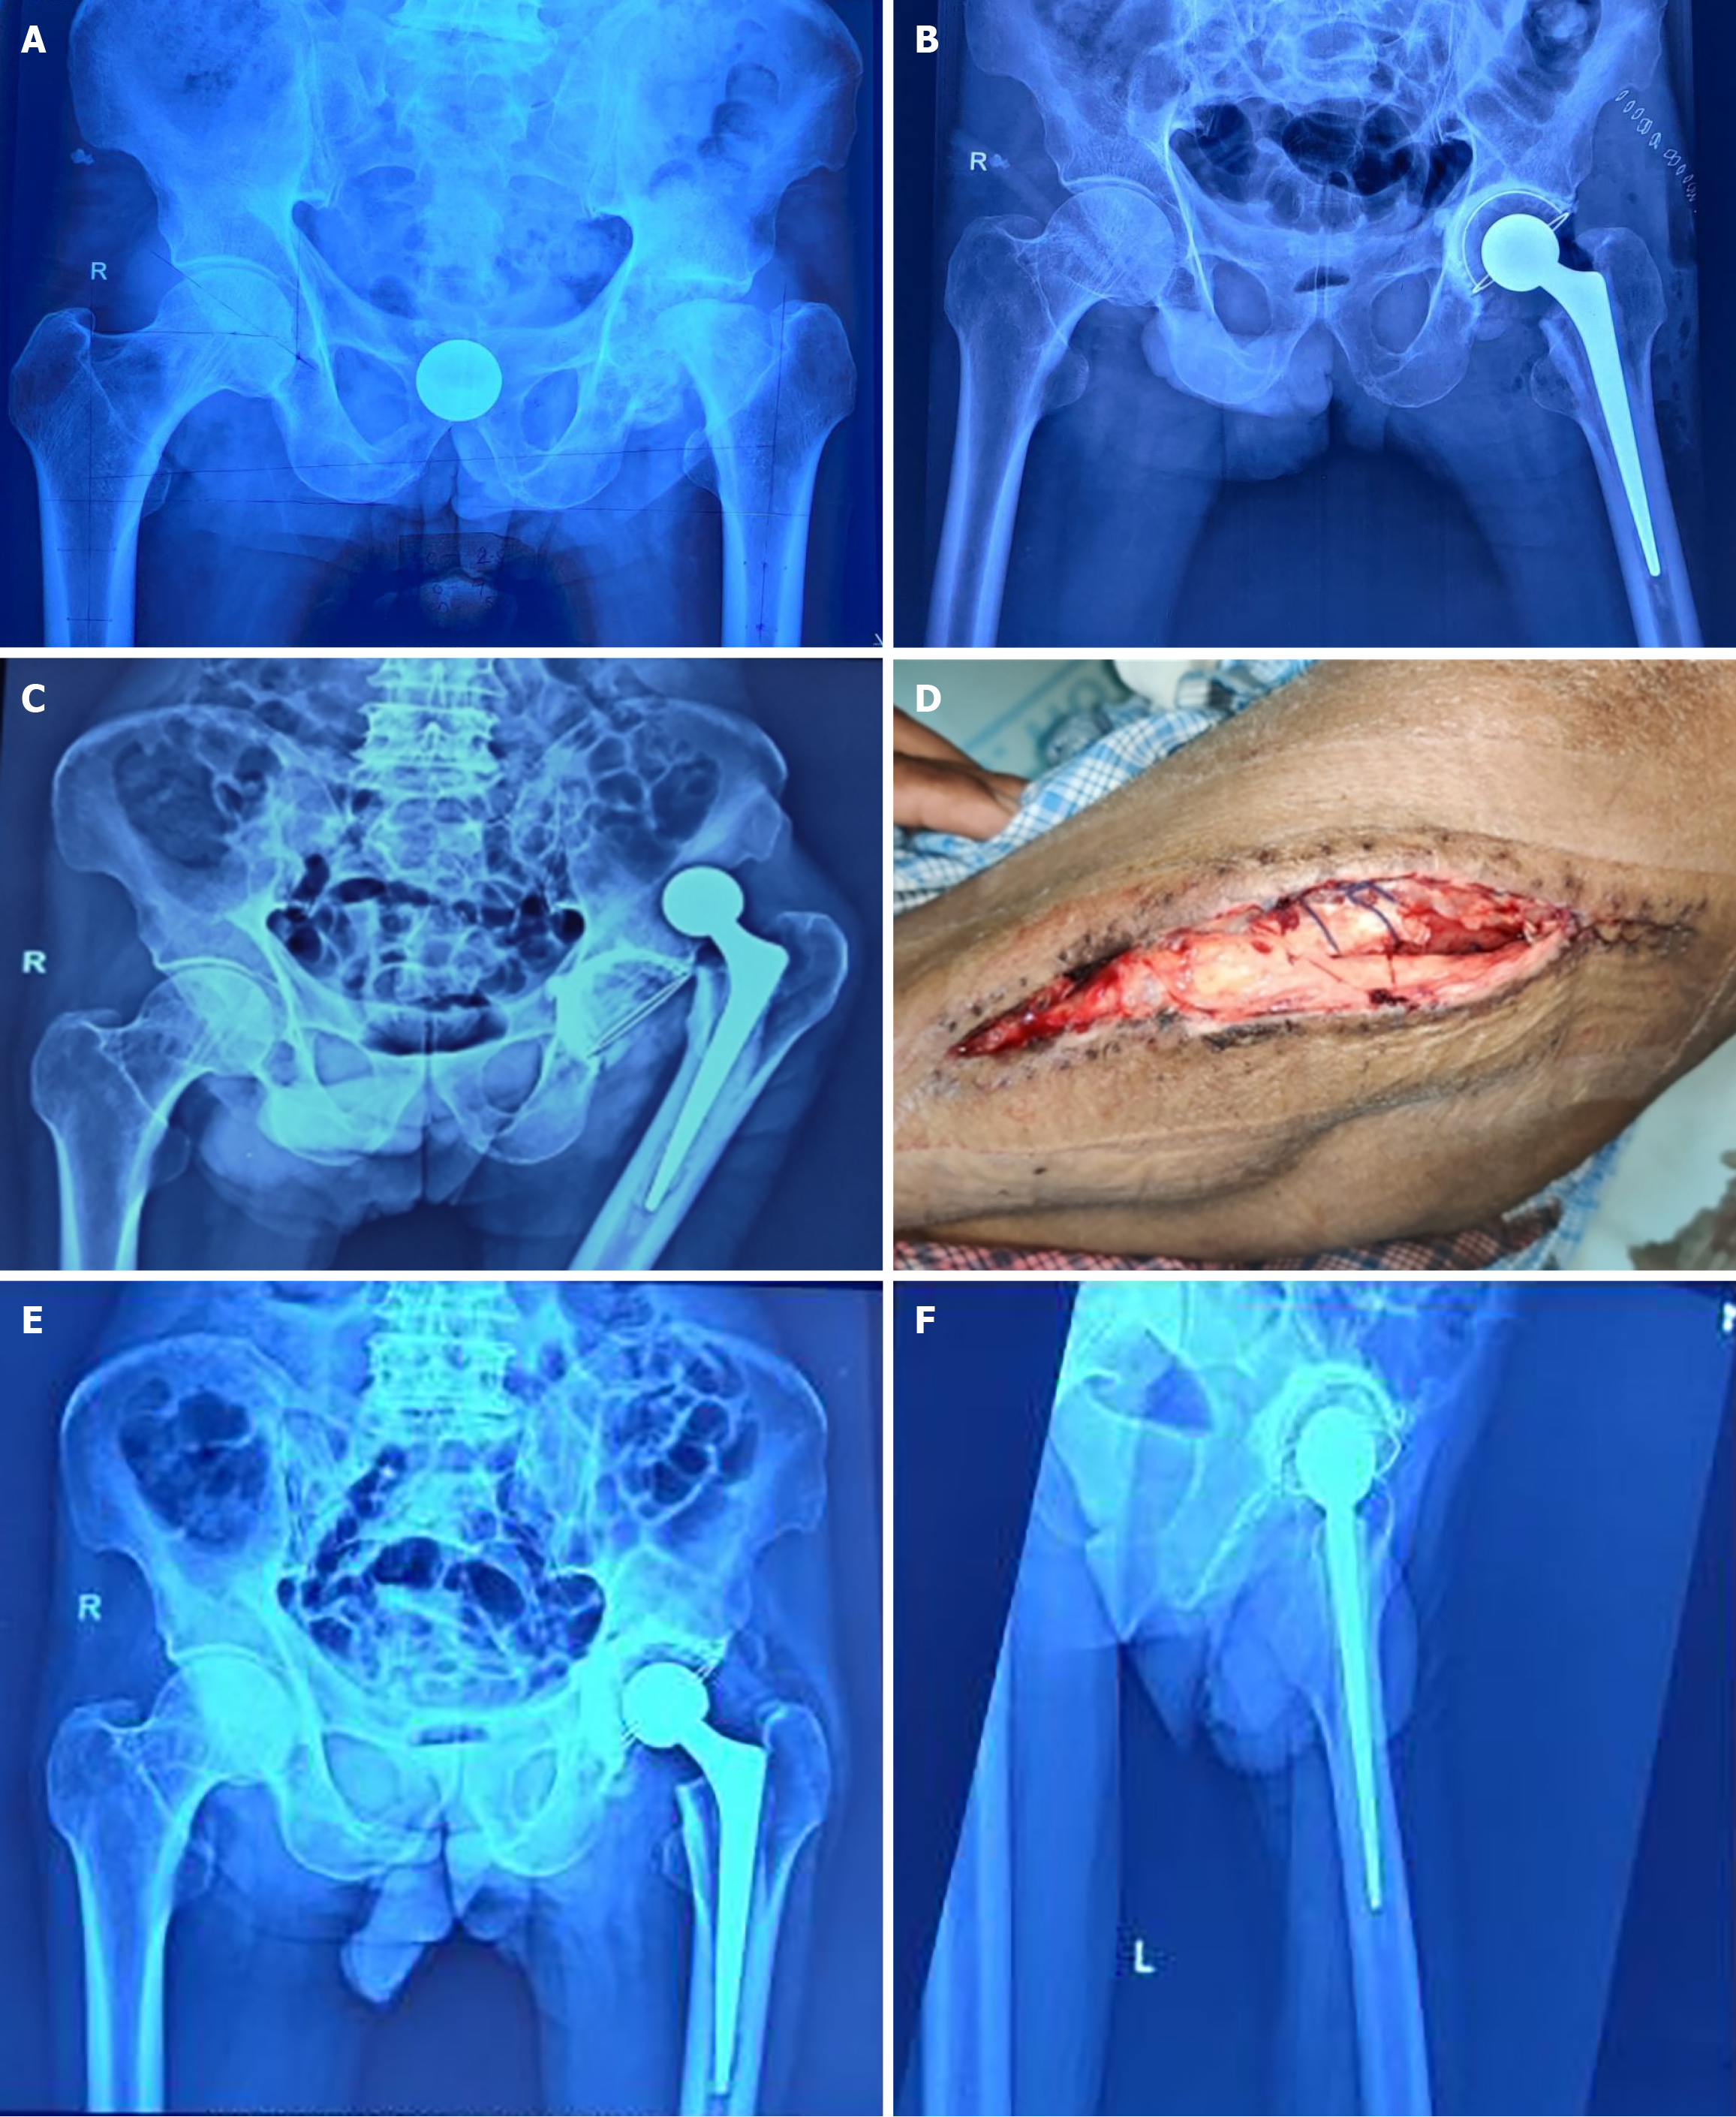

Joint dislocation

Eskola et al[38] have reported prosthesis dislocation in these patients and advise management depending upon the stability of THA components. One of our patients (a 55-year-old male) developed hip dislocation with wound dehiscence following a slip on the ground in the early postoperative period. The implant was stable; dislocation was reduced, and the wound was managed conservatively with a satisfactory outcome (Figure 6).

Figure 6

Figure 6 Imaging information of a 55-year-old male with advanced active stage 4 tuberculosis left hip. A: Pre-operative pelvic radiograph (anteroposterior view) of the patient; B: Immediate post-operative radiograph of the same patient following cemented total hip arthroplasty; C: Patient developed hip dislocation; D: Wound dehiscence in the early post-operative period following a slip on the ground. Closed reduction was done, and the wound was managed conservatively; E and F: Showing satisfactory outcome at 28 months follow-up.